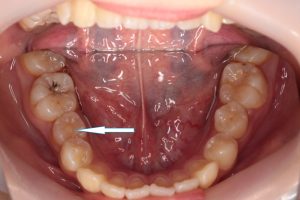

レントゲンにおいても、突起の中央の先端まで、神経の黒いスジがはいりこんでいます。

厄介なことに、突起の先端まで神経が入り込んでいることが多いです。

レントゲン画像で根尖性歯周炎の病巣、黒い影が見られます。